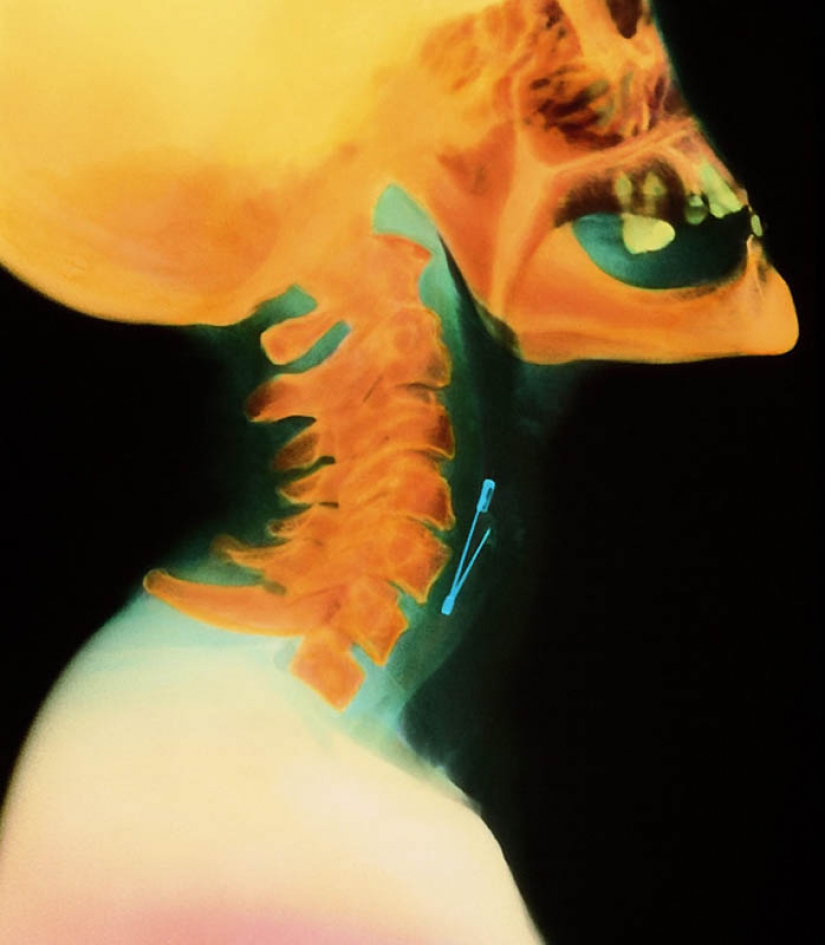

6. The pin on the woman's throat.